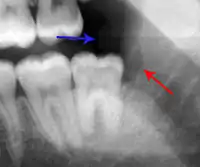

Apical periodontitis is acute or chronic inflammation around the apex of a tooth caused by an immune response to bacteria within an infected pulp.[20] It does not occur because of pulp necrosis, meaning that a tooth that tests as if it's alive (vital) may cause apical periodontitis, and a pulp which has become non-vital due to a sterile, non-infectious processes (such as trauma) may not cause any apical periodontitis.[10]: 225 Bacterial cytotoxins reach the region around the roots of the tooth via the apical foramina and lateral canals, causing vasodilation, sensitization of nerves, osteolysis (bone resorption) and potentially abscess or cyst formation.[10]: 228

The periodontal ligament becomes inflamed and there may be pain when biting or tapping on the tooth. On an X-ray, bone resorption appears as a radiolucent area around the end of the root, although this does not manifest immediately.[10]: 228 Acute apical periodontitis is characterized by well-localized, spontaneous, persistent, moderate to severe pain.[6]: 125–135 The alveolar process may be tender to palpation over the roots. The tooth may be raised in the socket and feel more prominent than the adjacent teeth.[6]: 125–135

- Radiographs utilized to find dental caries and bone loss laterally or at the apex.

Transillumination demonstrating fracture Decay (green) with apical abscess (blue)

Decay (green) with apical abscess (blue) Gutta-percha point indicating abscess origin